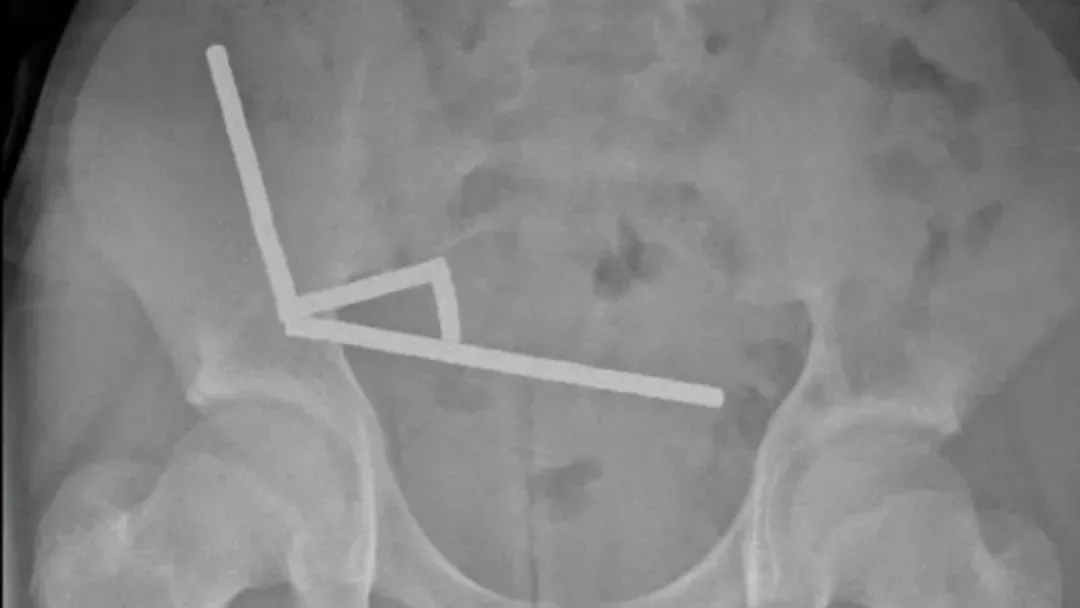

医生通过 X 光片观察到,男孩肠道的不同部位出现了四条线状的磁铁链。

手术中发现,这些磁铁链分别位于小肠不同区段及盲肠内。它们相互挤压,导致多处组织因血液供应不足而坏死,这种现象被称为压迫性坏死。

腹部 X 光片显示了磁铁分布情况 来源:Lekamalage et al.,?NZMJ, 2025

200 颗磁铁在患儿腹中形成了磁铁链。来源:Lekamalage et al.,?NZMJ, 2025